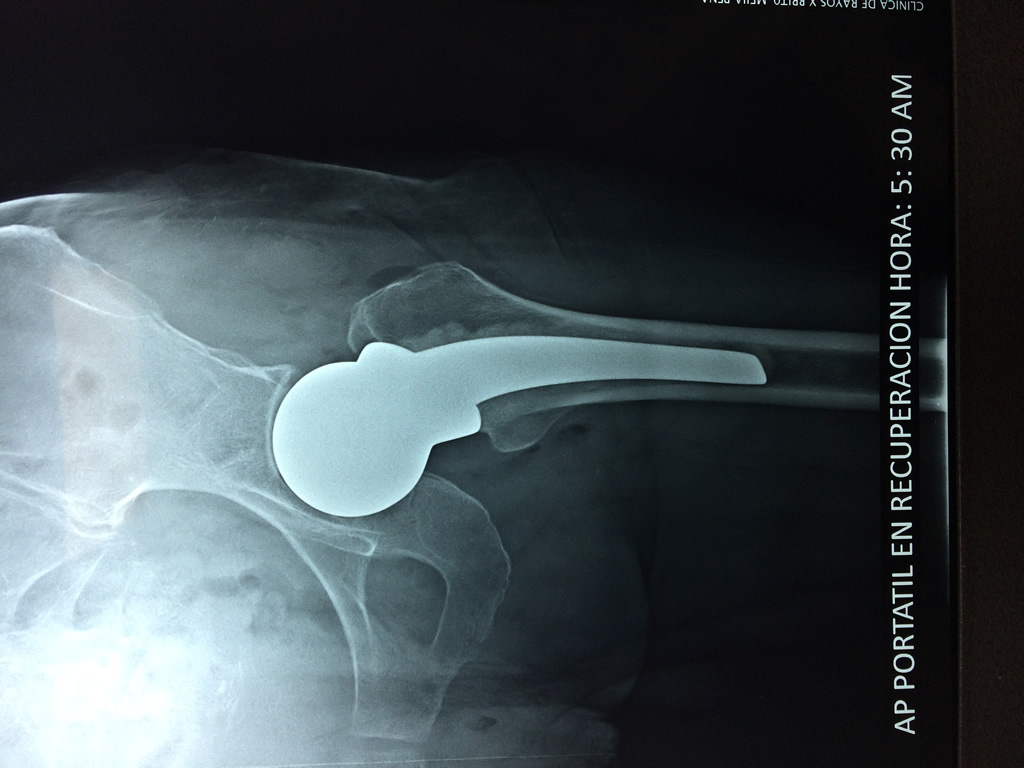

Cirugía de Fémur - Cadera

La cirugía de fractura de cadera se realiza para reparar una ruptura en la parte superior del hueso del muslo. Este hueso se denomina fémur.

Es parte de la articulación coxofemoral. Si una fractura de cadera no recibe tratamiento, es posible que deba permanecer en una silla o en la cama.